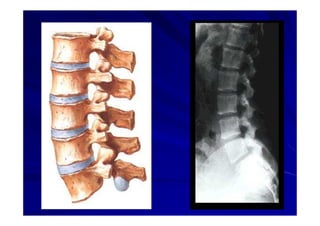

El documento presenta una introducción a la anatomía normal. Explica que la anatomía es el estudio de la estructura del cuerpo humano y clasifica los tipos de anatomía. Además, enumera los contenidos que serán cubiertos en el curso, incluyendo conceptos, posición anatómica, vocabulario, osteología, artrología y miología.